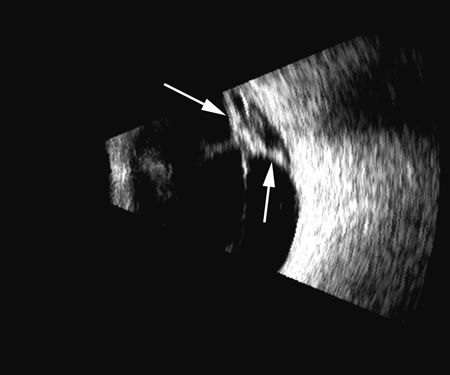

Vitreous foreign bodies are typically metal or glass objects, or intraocular lens implants. The ultrasound examination, with its better spatial resolution, is best performed following radiographic or computed tomography examinations in order to identify the location and number of foreign bodies. Ultrasonography is used to relate the position of a foreign body to the retina and lens and identify coexisting structural changes, such as retinal detachment. Metal and glass “absorb” or, more correctly, deflect sound, so that an anechoic area appears posterior to the foreign body. This area can act as an acoustic “pointer” to the foreign body (Fig. 18). A-scan or gray scale on B-scan shows a highly reflective surface of the foreign body. BBs and shotgun pellets often create a “ringing” artifact that can also act as a pointer leading to the foreign body.19 The foreign body can be easily demonstrated by lowering the gain; the foreign body remains, whereas other, less reflective tissue planes fade away due to a lower difference in acoustic impedance between tissues than metallic or glass foreign bodies. Most foreign materials have a higher density than the vitreous, and sound that passes through the foreign body may appear to move the succeeding surface forward because of the faster sound transit.

Fig. 18. A foreign body localized in the iris is easily imaged with high frequency. Characteristic trailing multiple echoes always point to the location of the body itself (arrow).